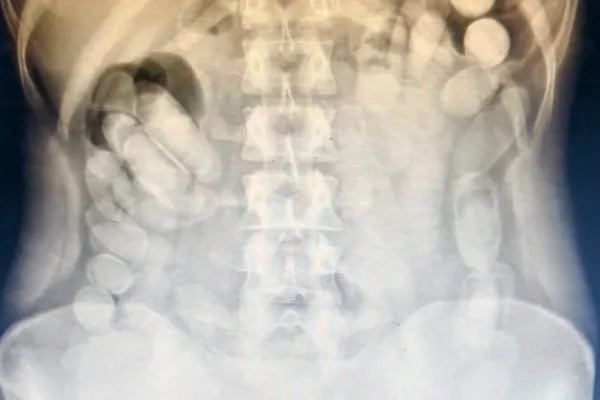

Detienen a una mujer en Tucumán con más de 100 cápsulas de cocaína en su estómago

También llevaba otros envoltorios en su bolso. Arrojaron un peso final de 1 kilo 388 gramos.